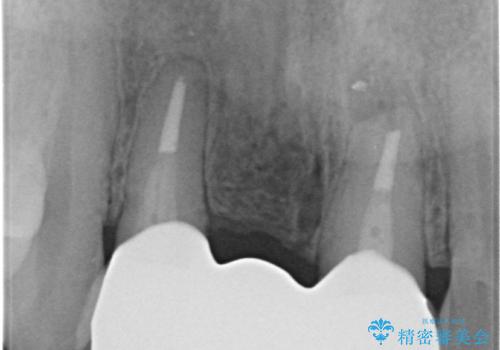

- 前歯のブリッジがすぐに外れる、歯ぐきが腫れている、見た目を良くしたい、と希望され来院されました。

現在装着されているブリッジを除去したところ、歯ぐきよりも上に存在する歯質(縁上歯質)が少なく、土台の形態の悪さや不適合などさまざまな問題があります。

根管治療を行ったのち、歯周外科を行うことで、欠損部の歯ぐきの厚みを出し、縁上歯質を獲得することで、長期的な予後の見込めるブリッジを製作できる環境を整備していきます。